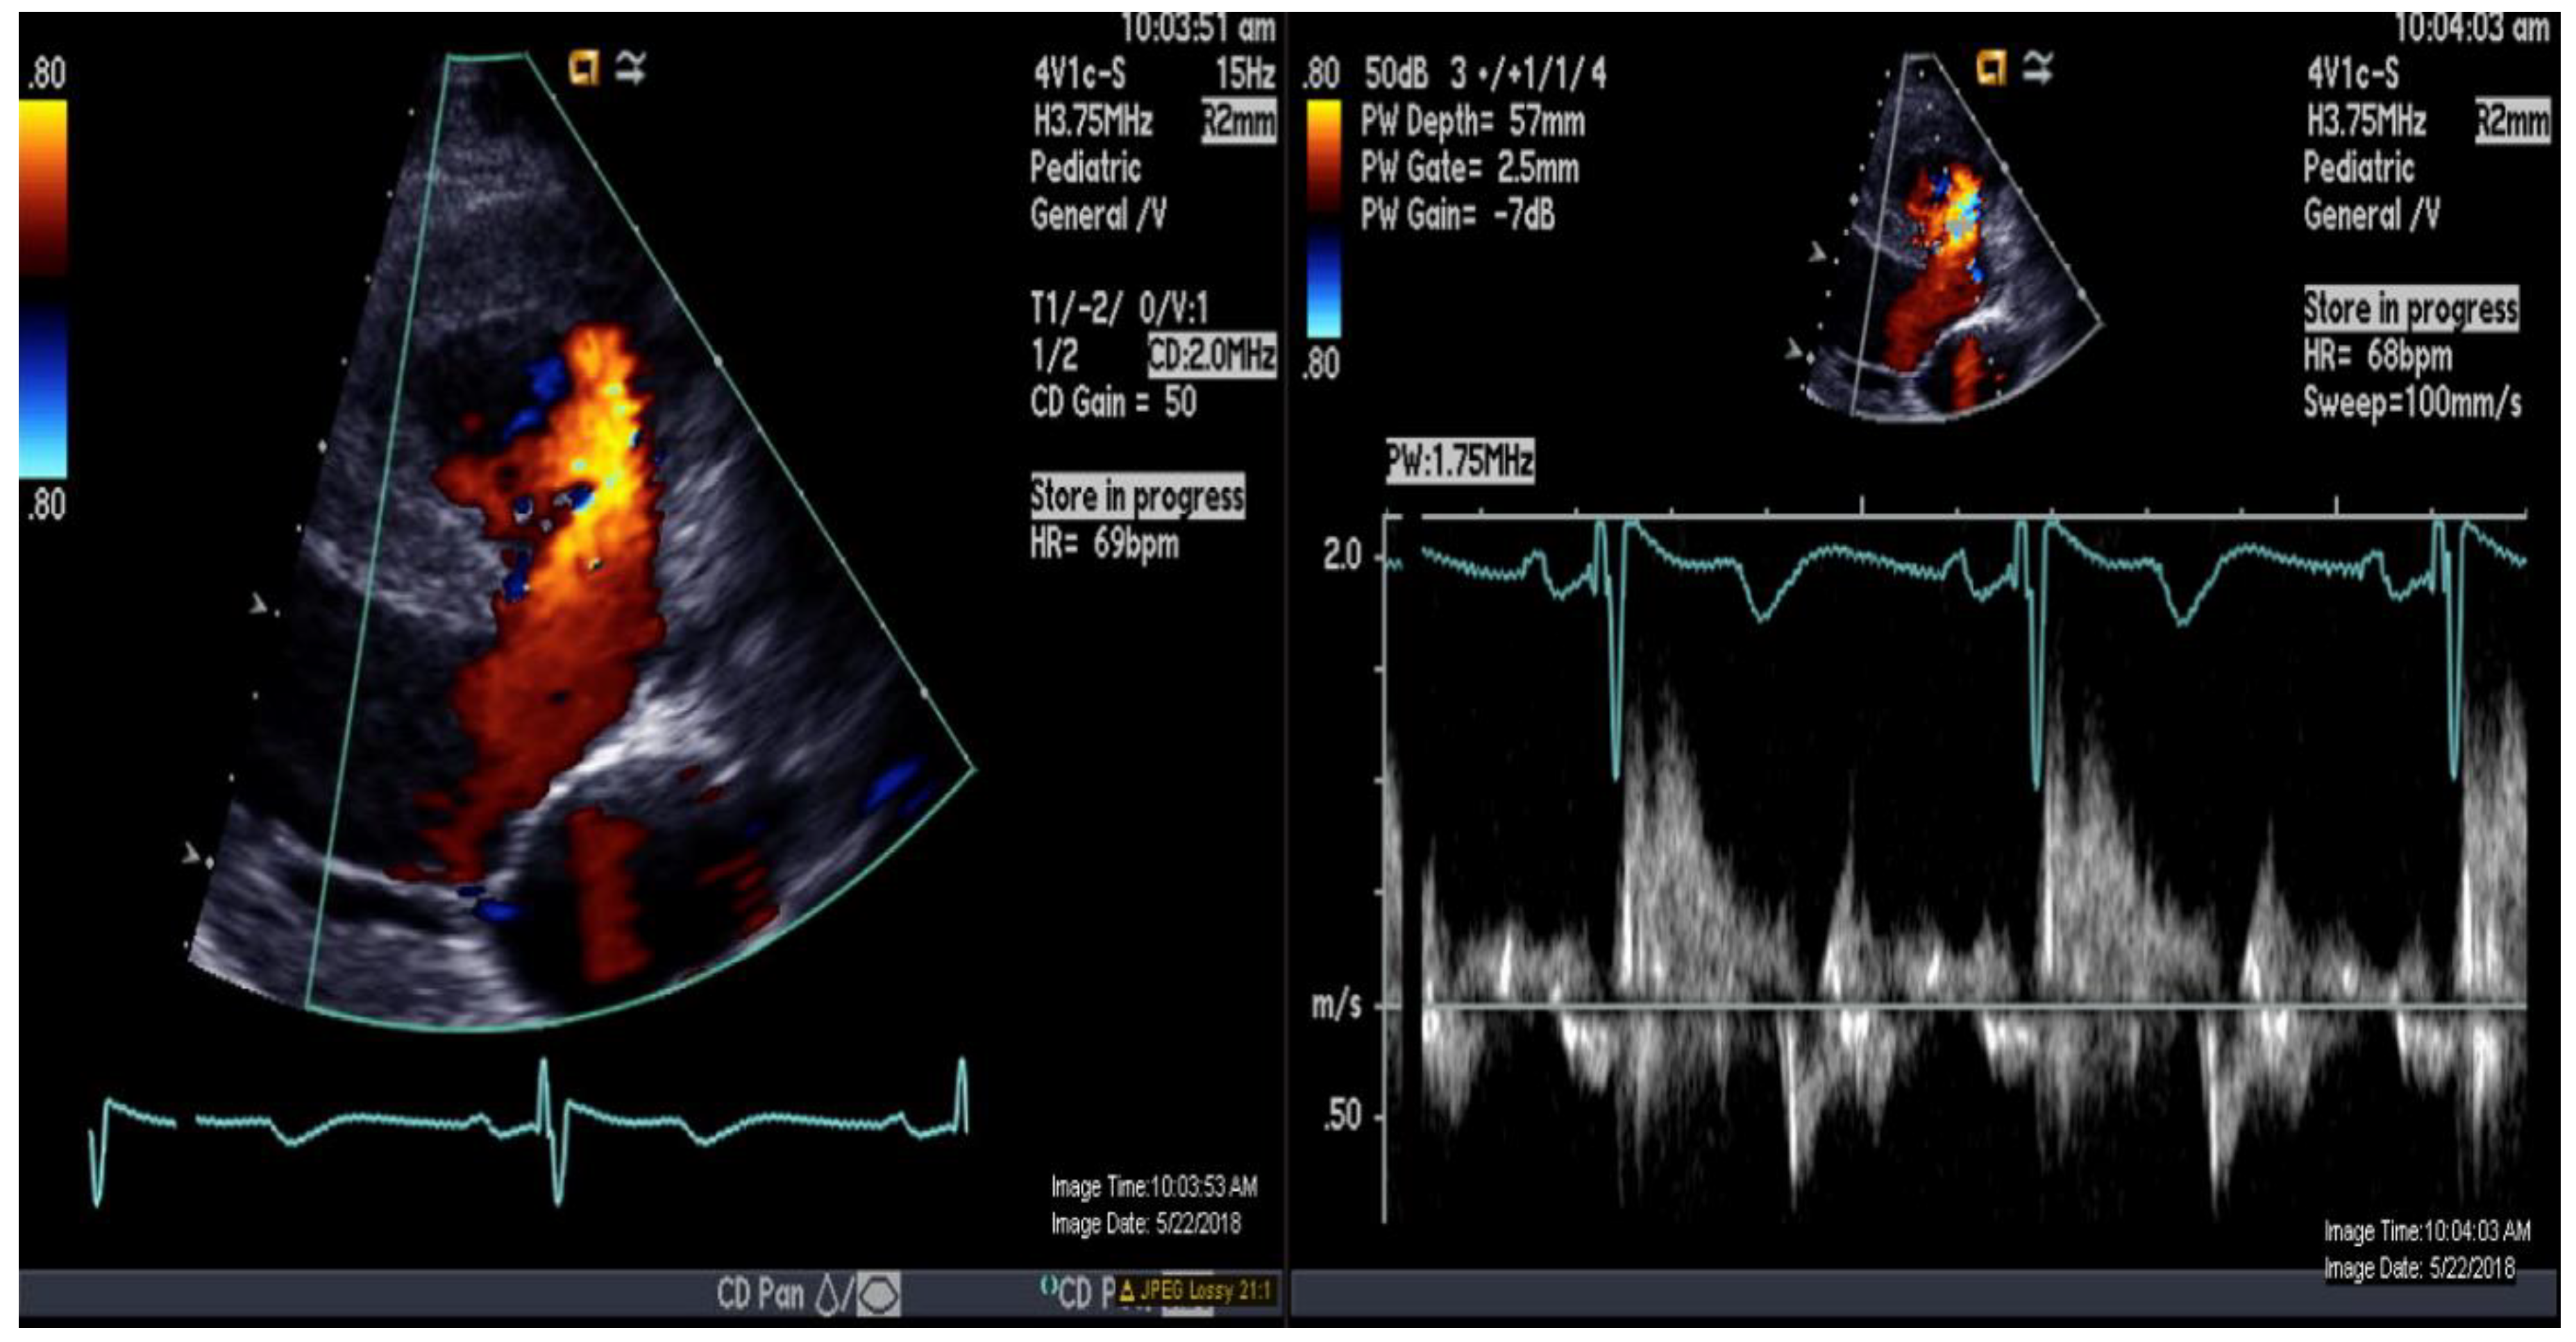

| VSD Flow L/min/m2 | 1.8 | 2.5 |

| PDA Flow L/min/m2 | 1.1 | 1.6 |

| Qp L/min/m2 | 5.4 | 7.8 |

| PVRi Woods U m2 | 8.7 | 6.8 |